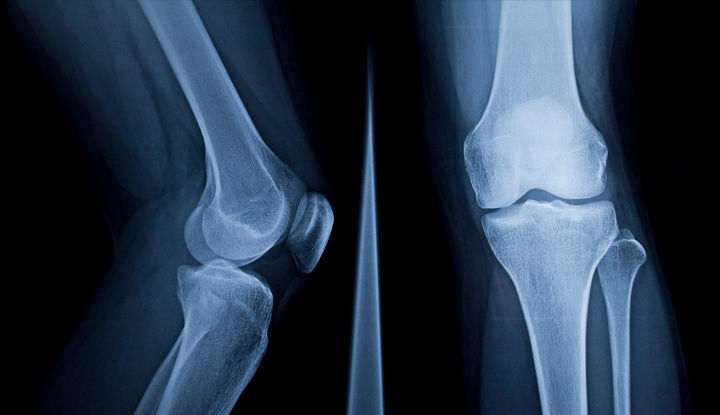

Blesková diagnostika a liečba chrbtice a kĺbov

Bolesti chrbtice a kĺbov patria medzi najčastejšie ochorenia, a preto správna diagnostika je prvým krokom k efektívnej liečbe. Vďaka našemu revolučnému stroju Esaote G scan Brio dokážeme odhaliť aj skryté problémy chrbtice a kĺbov, čím urýchlime cestu k úľave od bolesti a k návratu do plnohodnotného života. U nás získate komplexnú starostlivosť bez zbytočného čakania – všetko v jednej budove, s individuálnym prístupom a špičkovou technológiou.